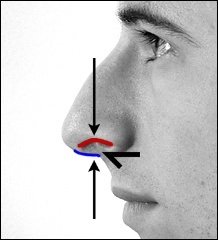

Mielőtt nagyobb acanthion. Ez az, amit úgy néz ki, a művelet során. Az ábrán a jobb ez sárga színű. Acanthion columella található, közvetlenül alatta, ahol a felső ajak határos az alapja az orrát.

Része a gerinc, amelyeket el kell távolítani jelzi a kék vonalon. Removal végezzük vésővel.

Fent és lent a beteg bemutatja fényképeket készített műtét előtt és után. Kék vonal a jobb szélén az alsó fényképekkel kijelölt columella és piros - szélén a bal orrlyukon. Az orrlyukak nyitott része által határolt két fekete nyilak. Mint látható, a műtét után orrlyukak nyitottak része csökkent, így az orr sokkal vonzóbb megjelenésű.